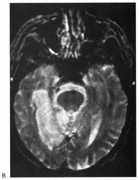

Cerebral blindness is distinguished from ocular disease by both normal pupillary light responses and normal fundoscopic examination. These may lead to an erroneous diagnosis of factitious visual loss. Associated signs of damage to parietal or temporal structures help to confirm cerebral blindness but may not always be present. Visual evoked potentials are of limited diagnostic value. They can be altered voluntarily by subjects without visual loss67 and can be normal in patients with striate lesions.68,69 They cannot differentiate between blind and seeing children with neurologic disease,70 and normal or abnormal results do not predict visual outcome.60,71 Absent evoked responses are rare and may only occur early in the course.70 Absent alpha rhythm on electroencephalography72,73 is reportedly a more sensitive diagnostic sign than abnormal visual evoked potentials.60 CT scans can be normal, but modern MR imaging with coronal images through the occipital lobe should reveal most striate or optic radiation lesions with complete and persistent visual loss (Fig. 16). Single photon emission computed tomography (SPECT) scans may reveal bilateral functional defects in cases with unilateral MRI lesions.74

Fig. 16. CT scan of man with cerebral blindness after a gunshot wound.